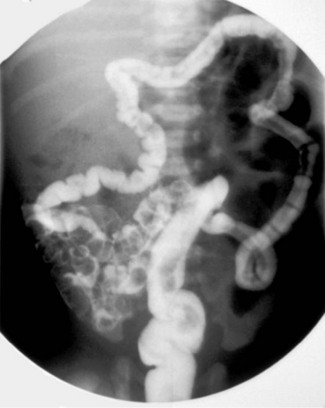

In meconium ileus, the distal ileum is obstructed by abnormal thick, viscid meconium and mucus plugs. About 95% of babies with this have cystic fibrosis and all babies with meconium ileus must be tested for it. The colon and rectum distal to the obstruction are of very small calibre. This microcolon results from the fact that no bowel contents have passed down it rather than any inherent abnormality (Fig. 50.6).

Fig. 50.6 Gastrografin enema in meconium ileus

Gastrografin enema X-rays in a baby with meconium ileus, showing the microcolon and the filling defects caused by abnormal meconium obstructing the distal ileum

The condition presents soon after birth with lower intestinal obstruction; the diagnosis is suspected when rectal examination reveals a patent but very narrow rectum. A Gastrografin enema may demonstrate inspissated meconium in the distal ileum and may also break up the material by a detergent-like action, relieving the obstruction. Laparotomy is required for unrelieved obstruction or any with signs of peritonitis. In most cases, the maximally dilated loop of ileum containing the inspissated meconium is resected and a primary anastomosis performed.